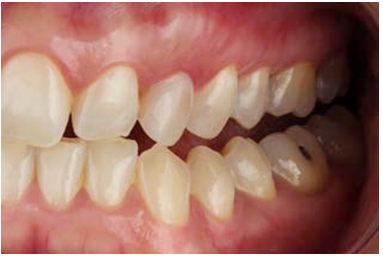

Parallel to these procedures, the selected composite resin must be warming up according to the manufacturer instructions, so that the clinician can quickly charge the pre-heated composite resin over the treated surface of the restorations (Figure 3.D), and so then position them on the teeth with soft pressure. At that moment, pressure must be done vertically and horizontally towards the tooth, allowing the exit of pre-heated resin through the interphase (Figure 5 and Figure 6). The excess of resin must not be light-cured and then cutted with a scalpel, this could leave areas of microleakage at the interphase in case of lack of adaptation. Eliminate and drain excesses of resin through the interphase could ensure sealing voids or gaps. A final control image after 1 year is shown in Figure 7.

Indirect composite resin veneer and fragment restorations can be safely used in the anterior dentition when indicated. The bonding procedure must be respected step-by-step to ensure high quality bonding to the tooth substrate and to achieve a long-lasting restoration. Finally, the correct assess of the clinical condition of a non-erupted canine and its restoration must include evaluation of functionality to ensure the success of the restoration.